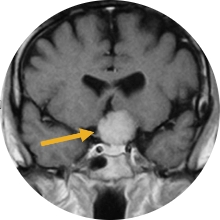

Mujer de 31 años, con crisis fármaco-resistentes desde los 2 años de edad. Sin antecedentes de interés.

La paciente es intervenida quirúrgicamente bajo control neurofisiológico para preservar la...

El abordaje se realiza a través de una craneotomía pterioral y se utilizan técnicas microquirúrgicas aspirador...